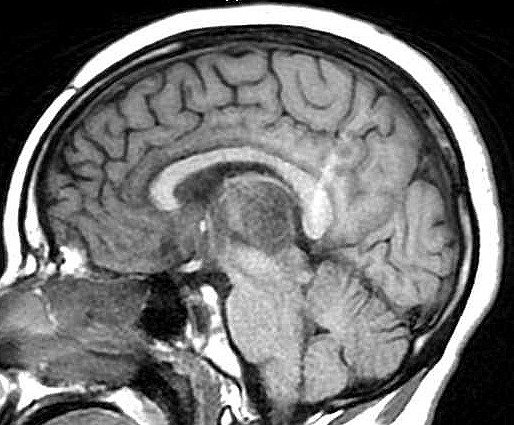

| Fem. 17a. |

| Nódulo sólido homogêneo preenchendo o III ventrículo, com limites precisos, com hipossinal em T1 e hipersinal em T2 e FLAIR, que se impregna por contraste paramagnético. Lesão menor implantada no assoalho do IV ventrículo provavelmente representa disseminação por via liquórica. |

| F. 17a. Tumor teratóide rabdóide atípico de III ventrículo. RM | HE | VIM, GFAP | HHF35, desmina, 1A4 | AE1AE3, EMA |